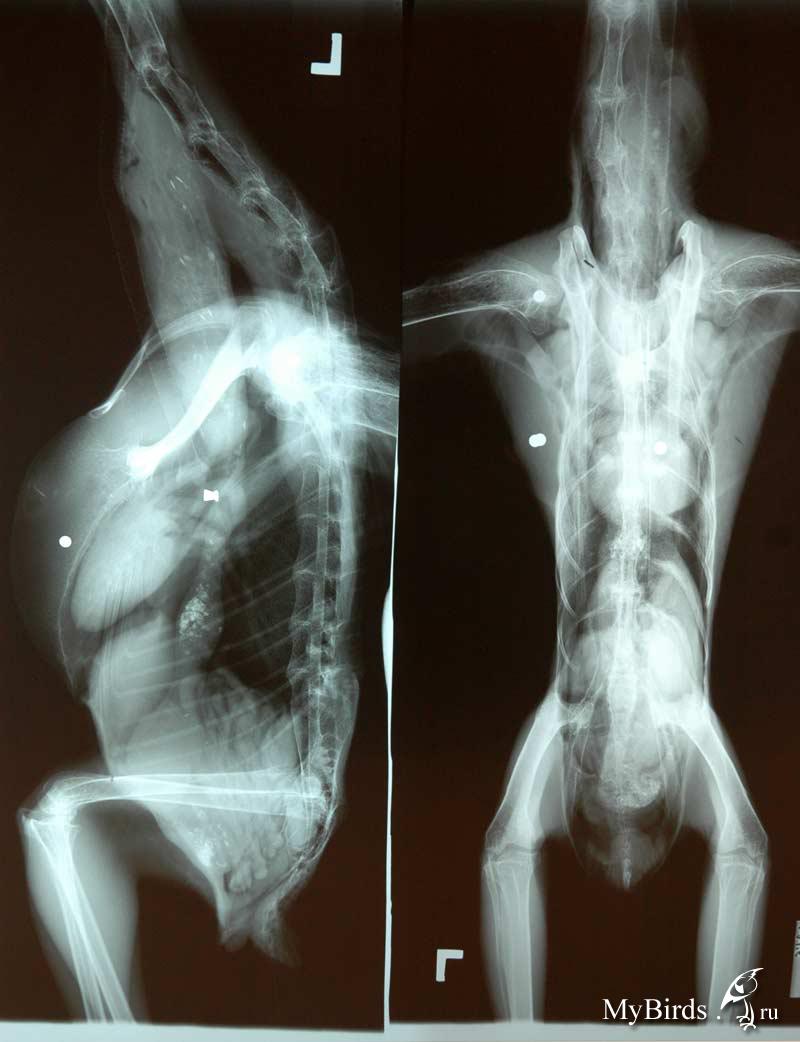

aleste Опубликовано 18 июля, 2010 Автор #84 Опубликовано 18 июля, 2010 С утра везем птичку на рентген, мне сказали что нужно сделать 2 проекции: дорсо-вентральная, птица на спине крылья раскрыты, и латеральная, птица на боку крылья отведены назад, ноги вытянуты вниз. С первой позой думаю справимся, а вот со второй ... даже незнаю как же ему отвести крылья назад, чтобы не дай бог не вывихнуть? Может Вы подскажете как птичку правильно держать во время рентгена. А может можно не отводить крылья назад? п.с. Как мне объяснили, снимки должны получиться примерно такими (это снимки не моей птички).

Cheshirski Опубликовано 19 июля, 2010 #85 Опубликовано 19 июля, 2010 А может можно не отводить крылья назад?905976[/snapback] Нет, мешать будут. Вообще, положение "крылья вверх" для птицы физиологично, и вроде еще не было случая, чтоб вывихнули или сломали.

aleste Опубликовано 19 июля, 2010 Автор #86 Опубликовано 19 июля, 2010 Рентген сделали. Врач, который делал рентген заметил, что недавно у попуая были сопельки и посоветовал обязательно сдать сопельки на бакпосев, (сопли были 15 июля, я об этом писал) а сегодня ноздри сухие, получится ли мазок из носа? Или делать его только в том случае, если сопли появятся снова? Получается нужно сделать два мазка: из зева и из носа?

Cheshirski Опубликовано 20 июля, 2010 #87 Опубликовано 20 июля, 2010 aleste, это фотоснимок неудачный, или сам рентген такой? Подробностей не видно, слишком контрастно... Получается нужно сделать два мазка: из зева и из носа?906490[/snapback] Достаточно будет из зева, там все соединяется. Проблема-то не в самом носу...